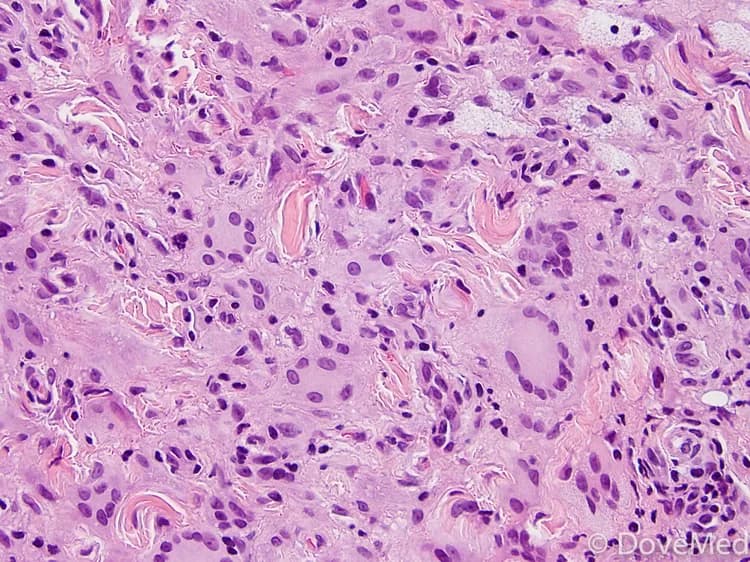

• Skin biopsy: A skin biopsy is performed and sent to a laboratory for a pathological examination. The pathologist examines the biopsy under a microscope. After putting together clinical findings, special studies on tissues (if needed) and with microscope findings, the pathologist arrives at a definitive diagnosis